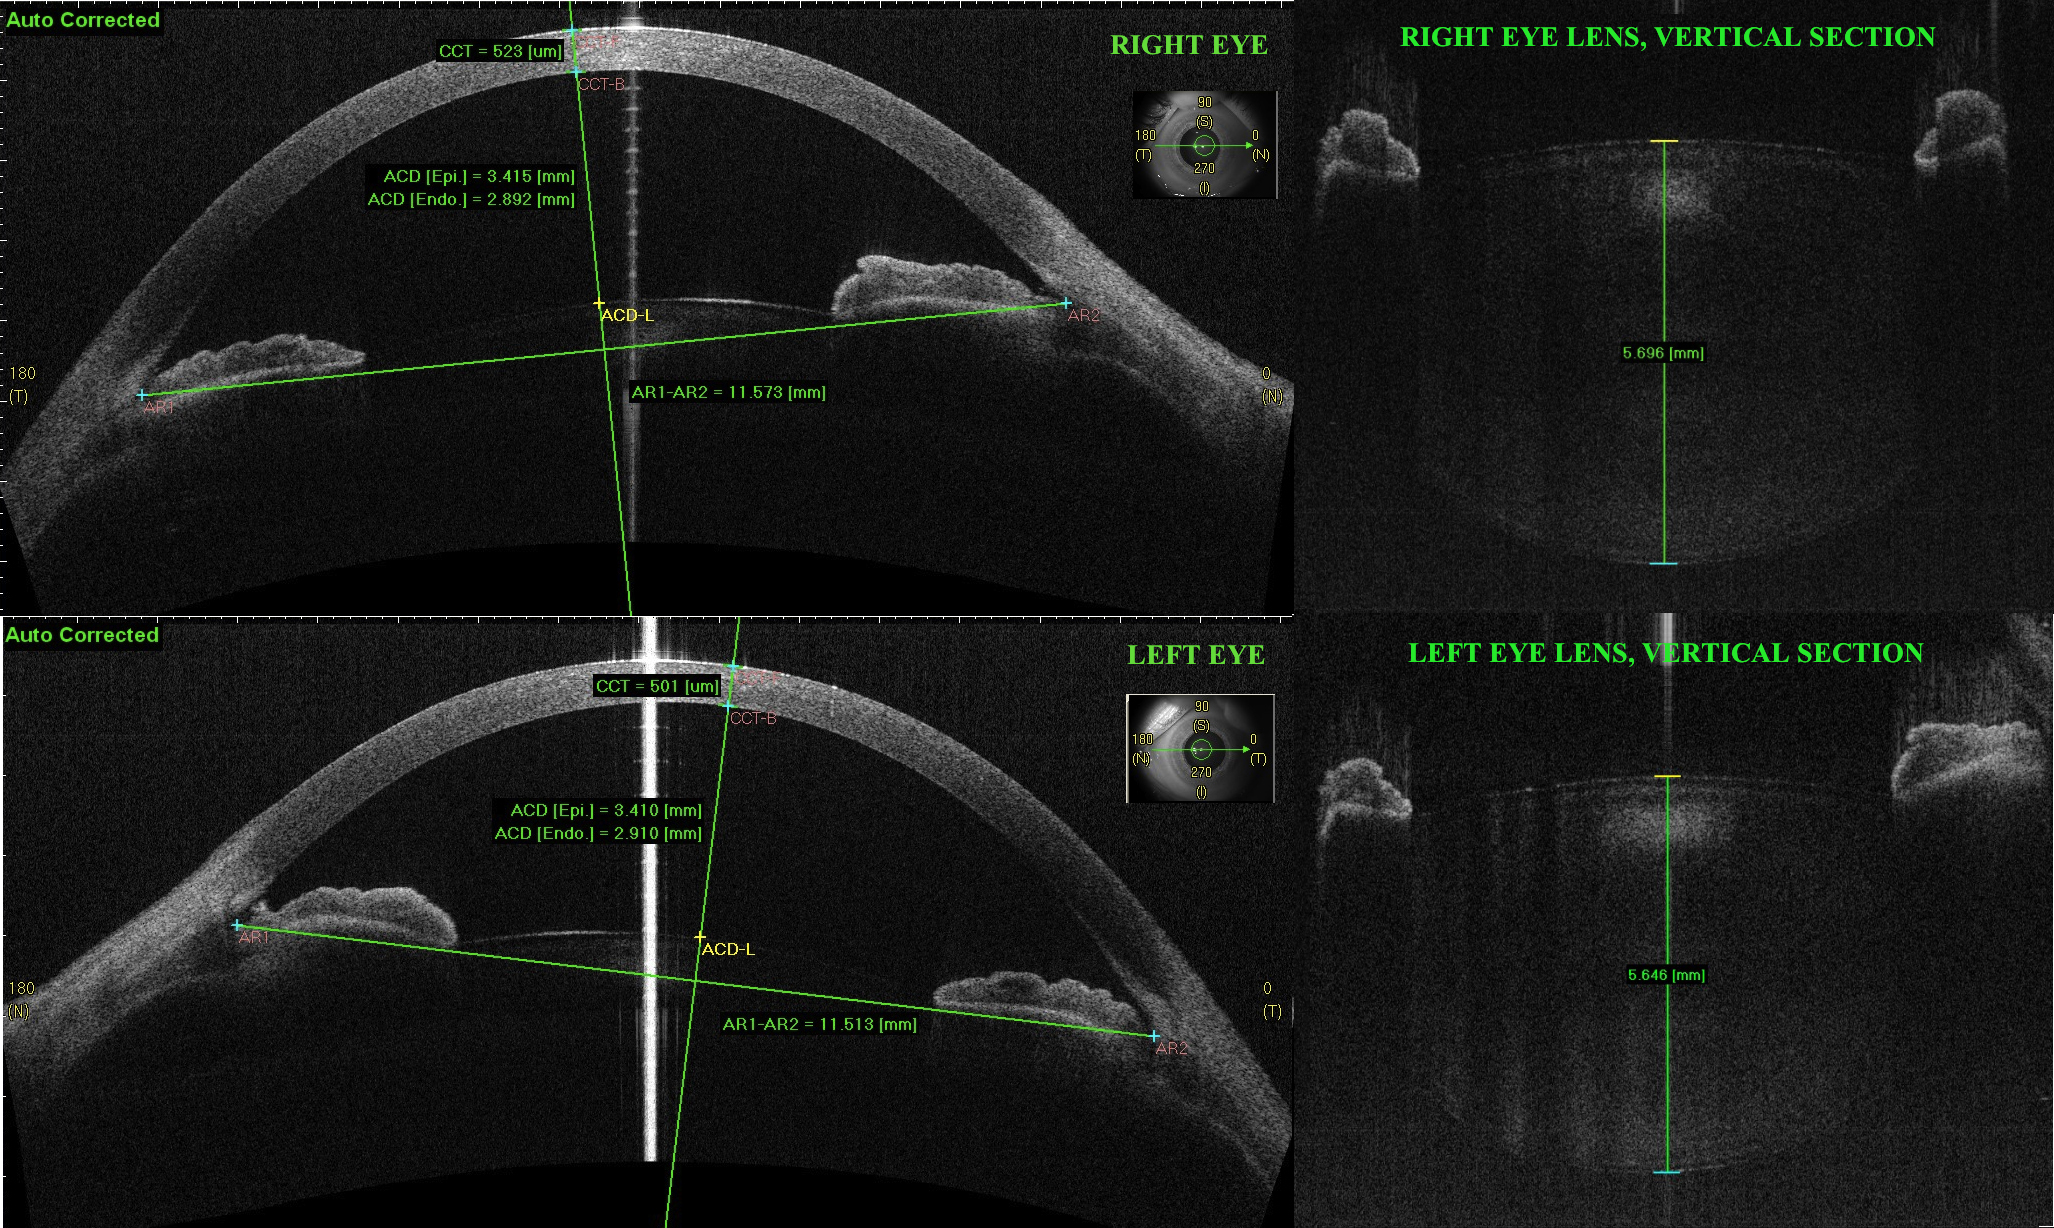

Figure 1. Analysis of the anterior segment of the patient's eyes at presentation with spectral-domain anterior segment optical coherence

tomography. The images are automatically corrected with the anterior segment optical coherence tomography (AS-OCT) software

accounting for the optical effect of the anterior and posterior surfaces of the cornea. On the left: horizontal B-scans of

the anterior chamber. CCT: central corneal thickness; ACD: anterior chamber depth, ACD [epi]: distance from the corneal epithelium

to the lens anterior surface; ACD [endo]: distance from the corneal endothelium to the lens anterior surface; AR1-AR2: anterior

chamber width, from temporal to nasal angular recess. On the right: vertical B-scans centered on the lens. Lens thickness

is measured along the fixation axis.